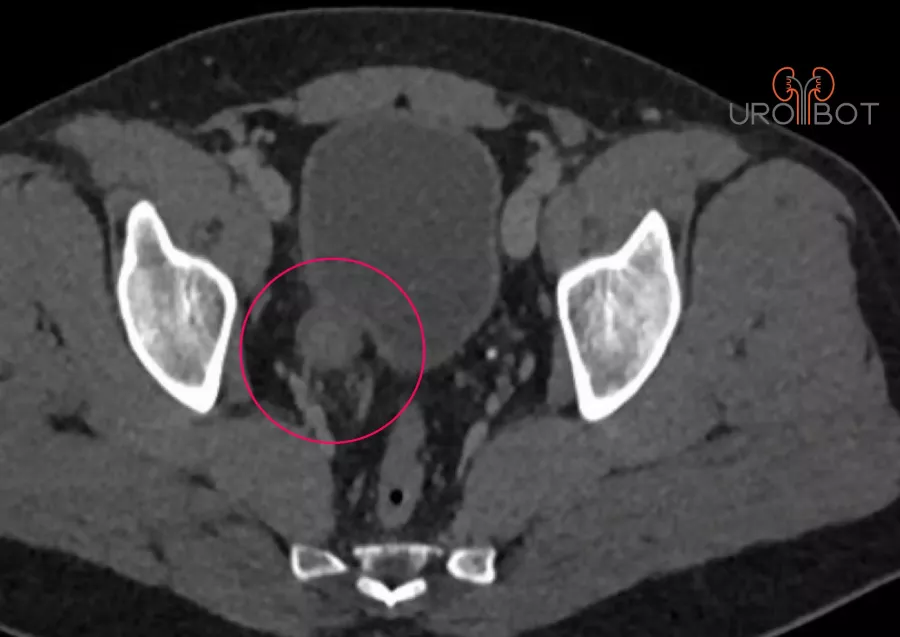

Harnleiterkarzinom

Bei einer Harnleiterteilresektion wird ein Teil des Harnleiters entfernt, weil er zum Beispiel durch einen Tumor befallen ist oder wegen einer Verengung nicht mehr durchgängig ist.

In Abhängigkeit der Lage im Harnleiter kann die Blase "verlängert" und hochgezogen werden oder der Harnleiter wird durch ein Stück Darm ersetzt.